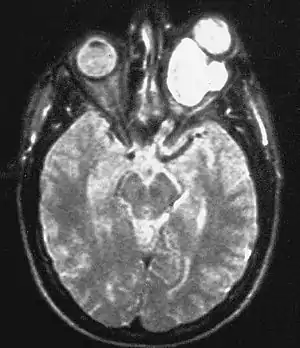

| Magnetic resonance image of a large retrobulbar optic nerve tumor causing massive proptosis | |

Optic nerve gliomas are diagnosed using magnetic resonance imaging (MRI) and CT scans.[5] The tumor adopts a fusiform appearance, appearing wider in the middle and tapered at the ends.[5] Enlargement of the optic nerve along with a downward kink in the mid-orbit is usually observed.[5] While CT scans allow for optic nerve evaluation, MRI allows for intracranial evaluation to observe if the tumor has extended to other regions such as the optic chiasm & hypothalamus.[6]